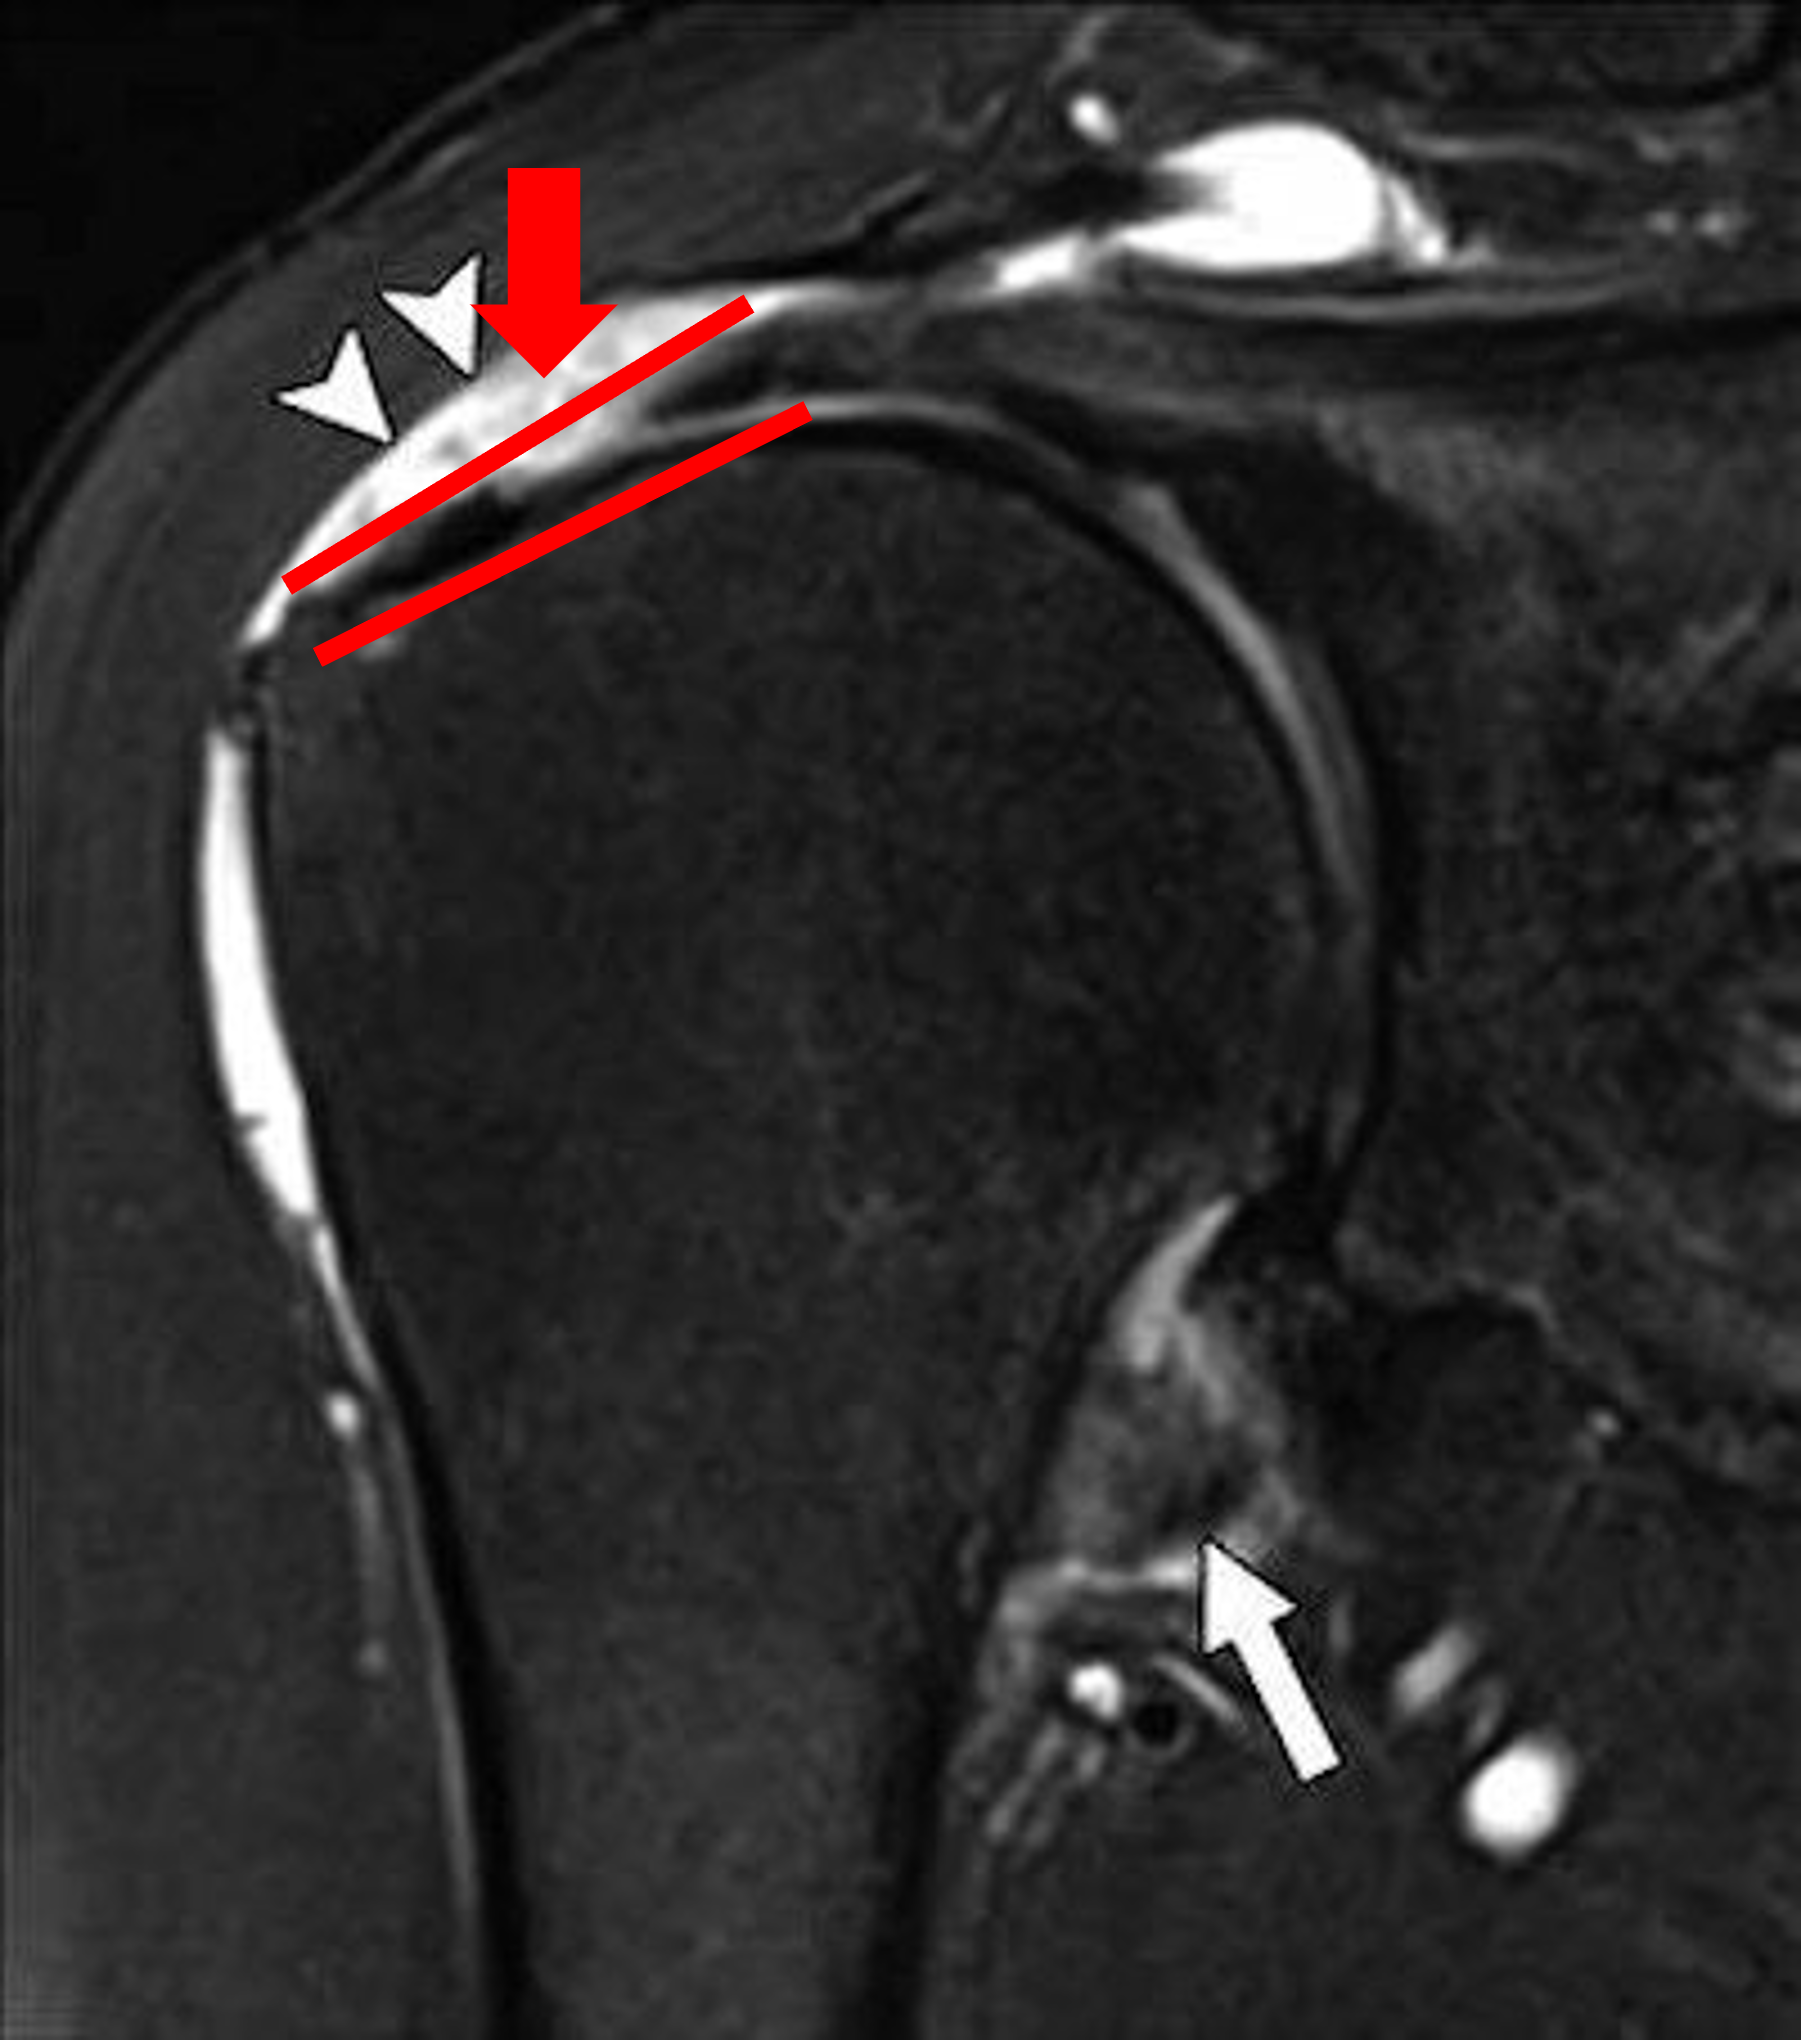

사실상 회전근개파열을 진단하는데 가장 중요한 진단 방법입니다. MRI는 우리 몸에 있는 물 분자들을 자기장을 이용하여 회전을 주어 그 신호를 이미지로 형상화 하는 기계입니다. X-ray는 X선을 쏴서 발생하는 그림자를 통해 이미지를 만들기에 뼈가 아닌 연부조직들, 즉 근육이나 인대, 관절낭 등은 이미지화 시킬 수가 없다는 점이 한계이지만, MRI는 이러한 연부조직 들 모두 수분을 가지고 있기에 이미지화 할 수 있는 장점이 있습니다.

MRI는 회전근개의 손상 부위를 정확하게 이미지화함과 동시에, 파열의 크기, 깊이, 그리고 주변 다른 조직의 손상을 동시에 관찰하게 해줍니다. 이는 결국 파열된 회전근개를 주사치료 정도만 해도 될 것인지, 아니면 파열이 커서 수술적 처치로 봉합을 해야할 것인지를 결정해주는 중요한 자료가 됩니다.